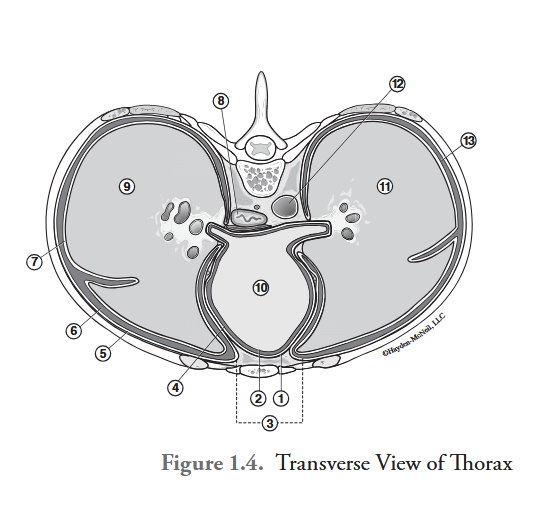

What is labeled #1?

parietal pericardium

What is labeled #2?

visceral pericardium (epicardium)

What is labeled #3?

mediastinum

What is labeled #4?

pericardial cavity

What is labeled #5?

parietal pleura

What is labeled #6?

right pleural cavity

What is labeled #7?

visceral pleura

What is labeled #8?

esophagus

What is labeled #9?

right lung

What is labeled #10?

heart

What is labeled #11?

left lung

What is labeled #12?

descending aorta

What is labeled #13?

left pleural cavity